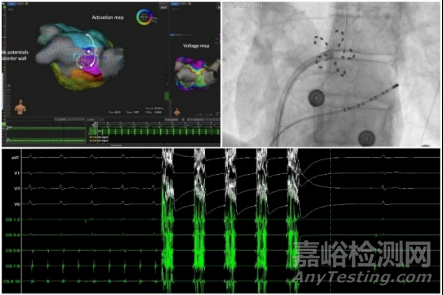

FARAPULSE脈沖電場消融新技術(shù)手術(shù)

在啟動儀式上,波士頓科學(xué)也帶來了PFA產(chǎn)品組合中的最新進(jìn)展:今年10月,帶有磁定位標(biāo)測功能的FARAWAVE NAV 心臟脈沖電場消融(PFA)導(dǎo)管獲美國FDA批準(zhǔn),新的FARAVIEW軟件模塊也獲得了FDA 510(k)許可。這兩款產(chǎn)品與波士頓科學(xué)現(xiàn)有的心臟標(biāo)測技術(shù)以及公司最新推出的OPAL HDx標(biāo)測系統(tǒng)(本段提到的3款產(chǎn)品尚未在中國內(nèi)地上市)完全兼容,將為心臟消融手術(shù)提供可視化支持。